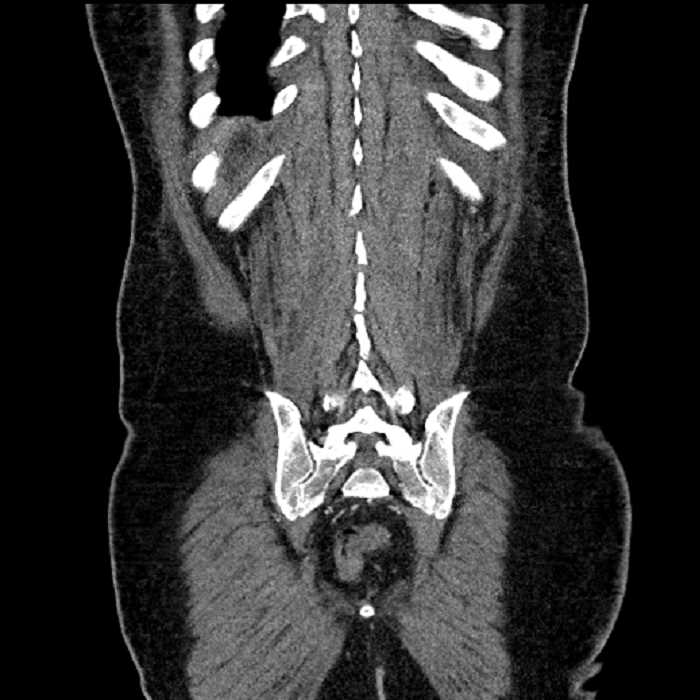

Age: 63

Sex: Male

Indication: Abdominal pain

• MSK

• No acute findings

• Ankylosis of both sacroiliac joints

• Circumscribed sclerotic lesion in the left anterolateral seventh rib without aggressive features, likely a bone island

Acute sigmoid diverticulitis complicated by a small contained perforation and a large abscess in the right hepatic lobe. Additional small subcapsular abscesses along the anterior margin of the left hepatic lobe.

High grade stenosis of the left common iliac artery. The left external and internal iliac arteries are patent.